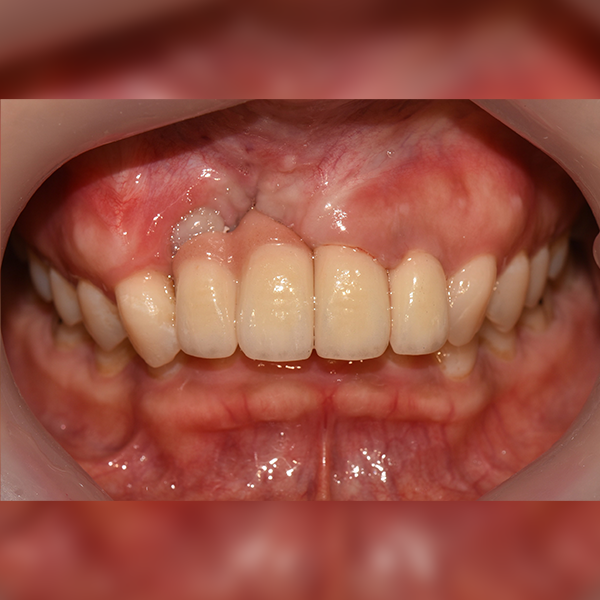

3. Trường hợp.111 Ông/Bà Triệu*Thiện, 30 tuổi 2018-11-30 / 2019-12-10

Trường hợp.111 Ông/Bà Triệu*Thiện, 30 tuổi 2018-11-30 / 2019-12-10

Before Before

After After